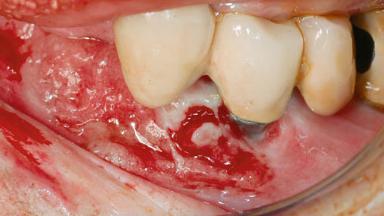

Peri-implant Carcinoma

Maximilian Moergel, Peer Wolfgang Kämmerer, Bilal Al-Nawas

Oral implants are highly successful and offer long-term benefits, especially in the rehabilitation of edentulous patients or patients with oral defects following ablative tumor surgery (Albrektsson and coworkers 1986), and also after radiation therapy (Schiegnitz and coworkers 2014). With the number of implants placed globally going into the millions, implant dentists have observed some rare adverse events. Although carcinogenesis around implants is an exceedingly rare phenomenon, we recently reported about 15 patients treated for carcinomas adjacent to implants at our clinical department over a period of fifteen years (Moergel and coworkers 2014). The following case represents a patient of this cohort; it discusses possible risk factors and makes suggestions for a recall schedule. A 70-year-old woman was referred to our outpatient department for evaluation of a rapidly growing macroscopic alteration of the mucosa in the left mandible.